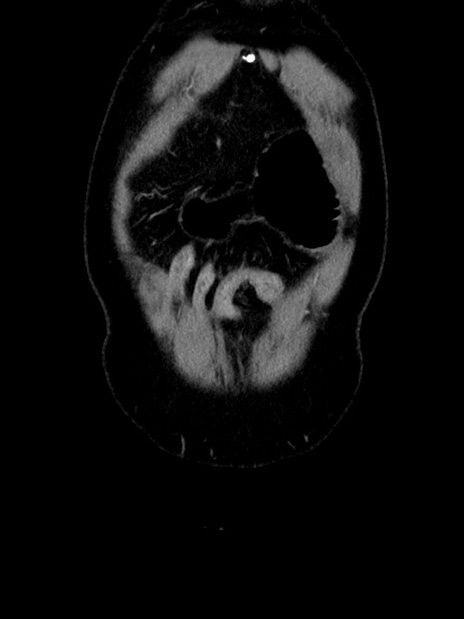

横断像